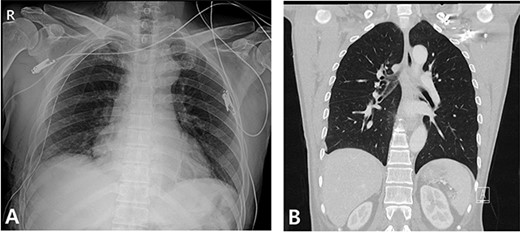

A 59-year-old man was admitted with multiple rib fractures and liver contusion due to a fall injury. He was standing on a chair for working at a farm, and it was knocked over causing him to fall and hit his flank against the corner of the chair. There was continuous pain while resting at the right flank and severe pain with pressure was noted, but no external wounds or bruises were observed. There were right 7th–11th rib fractures, scanty pneumothorax, minimal hemothorax and a 2-cm-sized liver contusion in abdomen and chest computed tomography (CT) scan (Fig. 1A, B). He was hospitalized for pain control and close observation in the general ward, and conservative management was initiated. Also, no significant changes were noted in the following daily follow-up chest radiographs. The patient suddenly complained of right-sided chest and back pain aggravation, cold sweating and fatigue 80 h after the traumatic injury. His mental status was alert, but v/s including systolic blood pressure (SBP) of 100–120 mmHg, heart rate (HR) of 40-60 beats/min and oxygen saturation of 100% during the admission changed to an SBP of 86/60 mmHg, HR of 88 beats/min and oxygen saturation of 97% when the symptoms occurred. Chest radiography was performed after the patient experienced aggravated symptoms, such as right-sided flank pain, cold sweating and fatigue. Compared to the previous scans, signs of increased opacification and peribronchial and parenchymal infiltrations were observed, which were indicative of hemothorax (Fig. 2A, B). We performed enhanced dynamic chest CT to identify any presence of active bleeding. On the chest CT scan, a large amount of hemothorax was identified in the right lung field along with multiple fractures of the right ribs. However, there were no signs of contrast leakage indicative of active bleeding (Fig. 3). Hemoglobin levels decreased from 13.1 g/dl on the day before the symptoms appeared to 11.5 g/dl at the onset of symptoms and to 9.4 g/dl after 2 h. Four packs of RBC transfusion and fluid were administered to the patient, and he was moved to the intensive care unit for close monitoring. And tube thoracostomy was performed, and 1600 ml of fresh blood was drained (Fig. 4A). The following day, 500 ml of blood was drained through the chest tube, but his v/s were stable (Fig. 4B). The amount of bleeding through the chest tube was decreased, but the drained fluid was fresh blood. And we thought that the remaining hematoma was not effectively drained, so the patient’s respiratory discomfort could persist and cause uneffective ventilation. And then we consulted with the Department of Thoracic Surgery, and video-assisted thoracoscopic surgery (VATS) exploratory thoracotomy was performed to identify the bleeding source caused by displaced rib and evacuate the large amount of hematoma. There was a large volume of hematoma within the pleural space and between the right lower lobe, diaphragm and fissure, but no active bleeding point was located. The fractured right 10th rib pierced through the pleural space and was displaced to the thoracic cavity, which was easily reduced. There was no injury surrounding the diaphragm, and although the general lung and chest wall contusions were severe, there were no signs of lung parenchymal lacerations (Fig. 5A–C). Chest tube drainage was serous, and there was no further bleeding. There were no signs of bleeding or any other abnormal findings on chest CT performed at the outpatient clinic, and the patient had no complaints of any symptoms (Fig. 6A, B).

Radiographic findings. (A) After chest tube insertion. (B) 12 h after chest tube insertion.